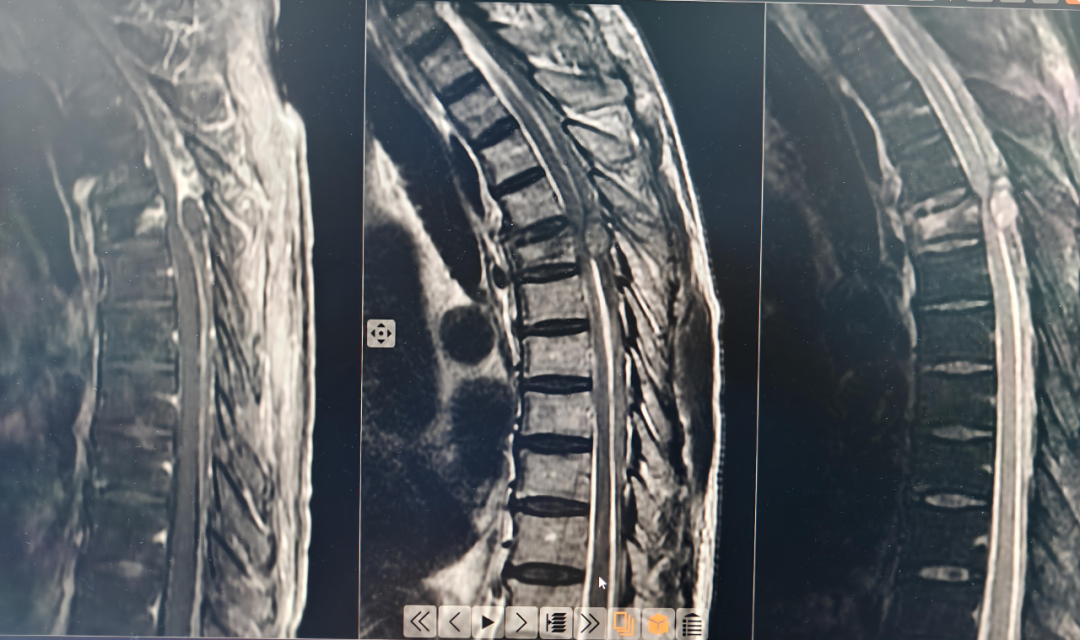

接诊翟立主治医生详细询问病史及查体后迅速为王爷爷安排急诊检查,胸腰椎核磁共振(MRI)结果却不容乐观:胸5椎体压缩性骨折,更危险的是,骨折导致了椎管内血肿形成!这个不断增大的血肿像一个冷酷的“钳子”,死死压迫着胸段的脊髓。这正是导致老人胸部以下感觉丧失、双下肢完全瘫痪、大小便功能障碍的罪魁祸首。医学上,这种情况称为急性胸部脊髓损伤。

表1胸5骨折、后方椎管内的椭圆形信号即为压迫脊髓的血肿